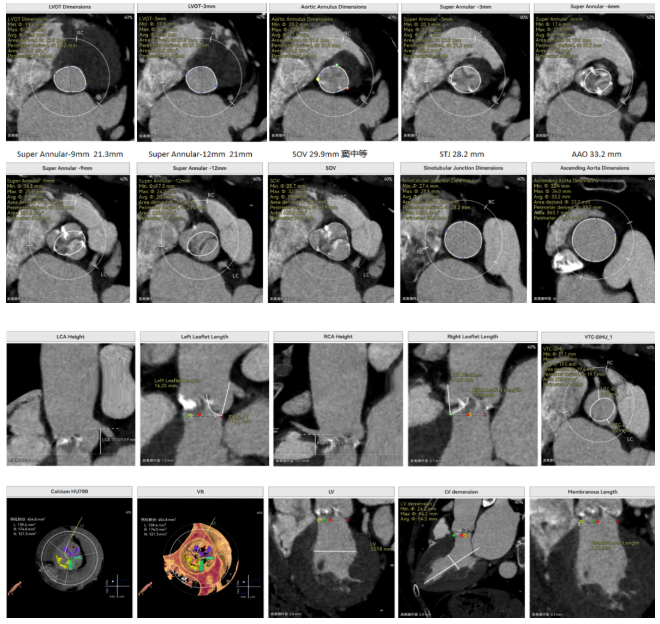

修建成教授 南方医科大学南方医院(点击查看专家详细简历) 细微之处防未然,创新携手寸寸安: 愈知临床无小事,任何风险的蛛丝马迹,都可能牵动全局。我常对团队说,真正的严谨,是将所有潜在 scenario 视作必然,在术前便一一拆解、化解 —— 如同在堤坝溃决前便筑牢每一寸基石,让风险连萌芽的机会都没有。 此次应用全球首创的预装干瓣,是基于对患者的综合考量,拥抱创新,实践创新,让创新携手助力“万全之策”的重要环节。 术前推演需要结合器械的特性:深度了解才能得心应手,结合患者基础病的相互影响并落实到术后 72 小时的并发症预警,每个环节都要像精密齿轮般咬合无误。这份 “穷尽万一” 的准备,从来不是对完美的苛求,看似耗时费力,实则是对生命最质朴的承诺 ——以医者的周全,携手创新的产品,为患者的万无一失不断努力! 患者病史 因 "反复胸闷伴活动后呼吸困难 3 年" 入院:患者 3 年前无明显诱因反复出现胸闷,部位在前胸,有憋气感,间有心悸,伴有活动后呼吸困难;外院就诊,查心脏彩超示 "主动脉狭窄、二尖瓣关闭不全"; 既往有高血压 20 余年,长期服用氨氯地平阿托伐他汀钙片降压治疗;有糖尿病 1 年,长期服用二甲双胍、阿卡波糖降糖治疗。 术前超声提示:主动脉瓣增厚、钙化并狭窄(重度)及关闭不全(轻度) 术前超声提示:主动脉瓣增厚、钙化并狭窄(重度)及关闭不全(轻度) 术前CT Type1型(R-N)二叶瓣,中度钙化集中在左窦瓣叶边缘及右无交界处,主动脉根部直径21.6mm,LVOT直径22.2mm,瓣上限制逐渐增大;双侧冠脉开口高度可,瓣叶短,窦部宽度足够,双冠VTC空间>4mm,预估冠脉风险小。 左室腔小,室间隔膜部短,有一定PPI风险;外周双侧入路无明显迂曲,双侧髂外动脉存在散在钙化、股动脉直径大,右股低分叉,能够支持20F大鞘通过。 手术策略 推荐右侧股动脉为主入路,放置20F大鞘,左侧为辅助入路,常规穿刺;使用20球囊预扩,预装AV23瓣膜;左右重叠位:RAO 1° CAU 28° ;右窦居中位:LAO 22° CAU 0° ;左冠切线回调:LAO 35° CRA 17° ;心室小,术前术中积极补液调整容量,做好循环崩溃处理准备。 手术过程 主动脉根部造影 20mm球囊预扩 - 无腰无漏 瓣膜初始定位 工作位观察瓣膜 - 冠脉通畅,位置合适 最终造影观察 - 无瓣周漏、挂钩处于最右方-Commisural Alignment 术前压差120mmHg,术后压差2mmHg。 Prostyle A®预装干瓣——助力临床最优化解决方案: 平衡的径向支撑力:该病例为TYPE 1型二叶瓣,对产品的径向支撑力是一种考验,术后影像彰显Prostyle A®综合设计带来平衡的径向支撑力,轻松应对高钙化病变,符合中国国情,为二叶瓣患者带来信心保障; 轻松过弓,精准可控:该病例主动脉弓角度可,但弓距小,考验产品的通过性能,术中顺利过弓,未使用snare轻松过弓; 预装干瓣 便捷顺安:金仕生物专利抗钙化技术运用纳米技术去除组织内的细胞碎片和磷脂,封闭游离醛基,从根本上阻断了瓣膜钙化的多项因素,显著提升了瓣膜的耐久性;同时,相比较传统戊二醛保存方式,干式存储最大限度的保留心包的亲水亲油平衡,还原组织天然曲柔性,进一步保障了瓣叶开合,保证长期耐久性。